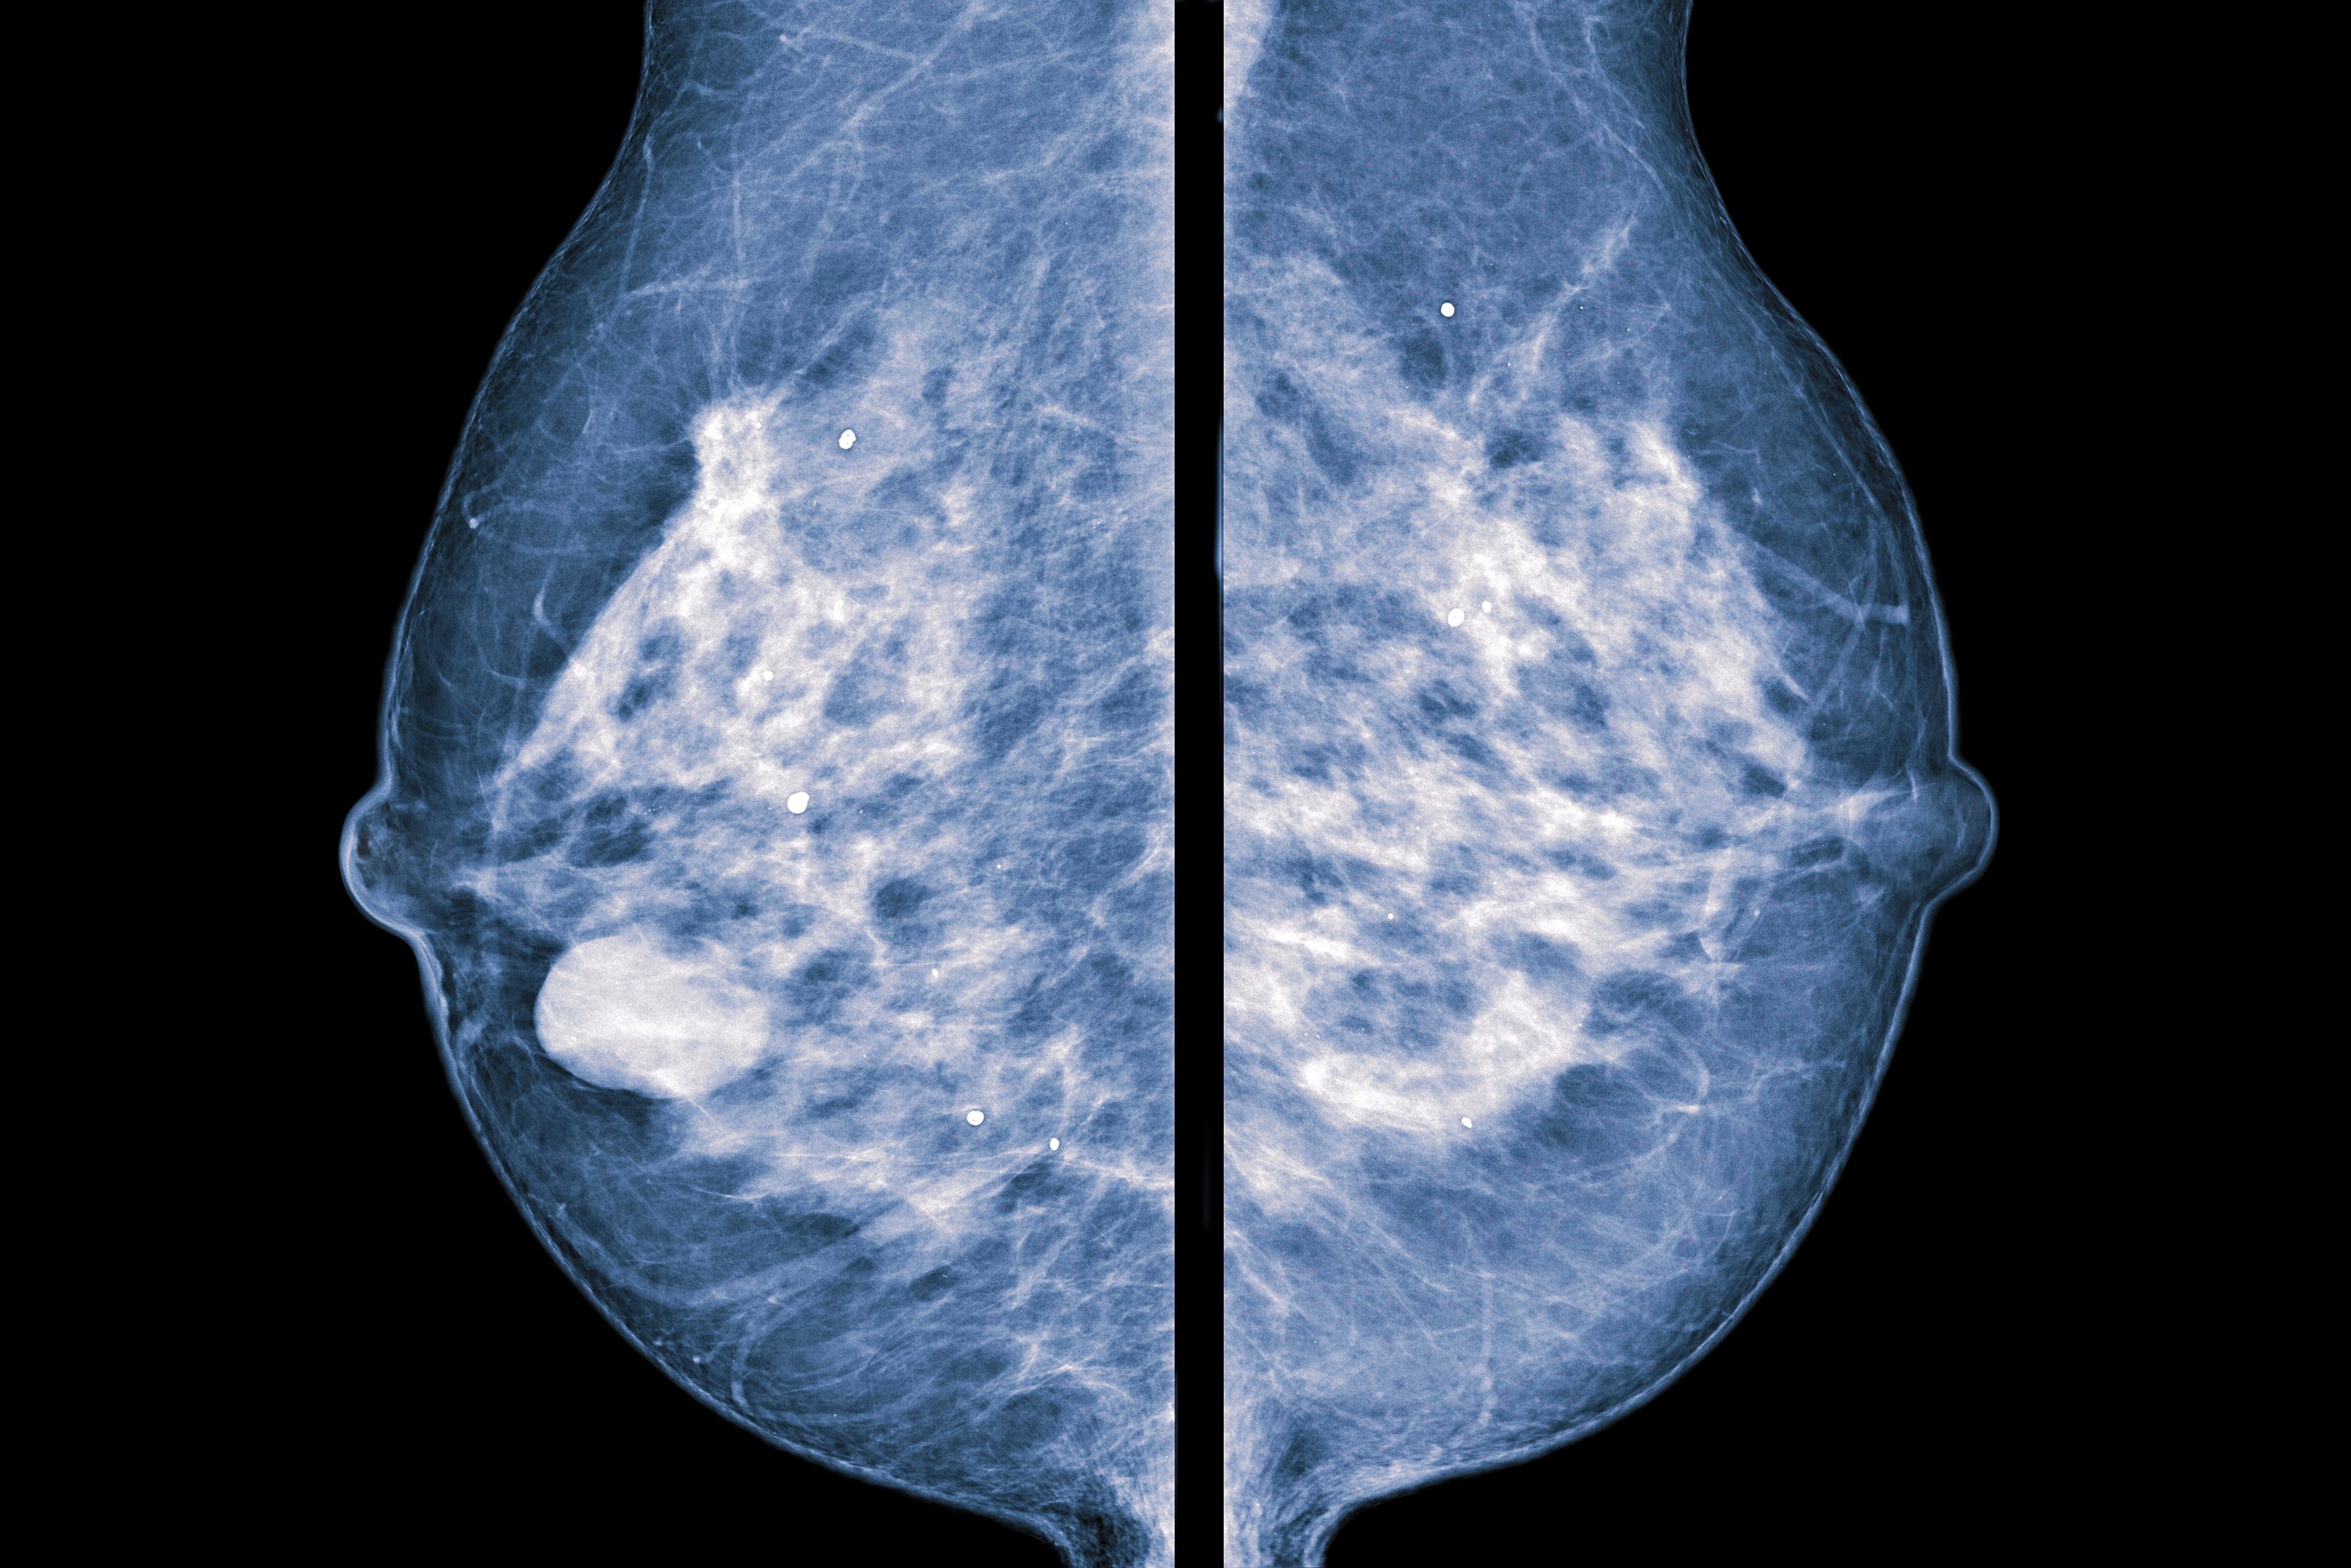

How to prevent calcium deposits. Natural treatments for calcium deposits can break down deposits, reduce inflammation and relieve pain. If you’re 65 or older, your healthcare provider may recommend. They’re common and often show up on a routine mammogram.